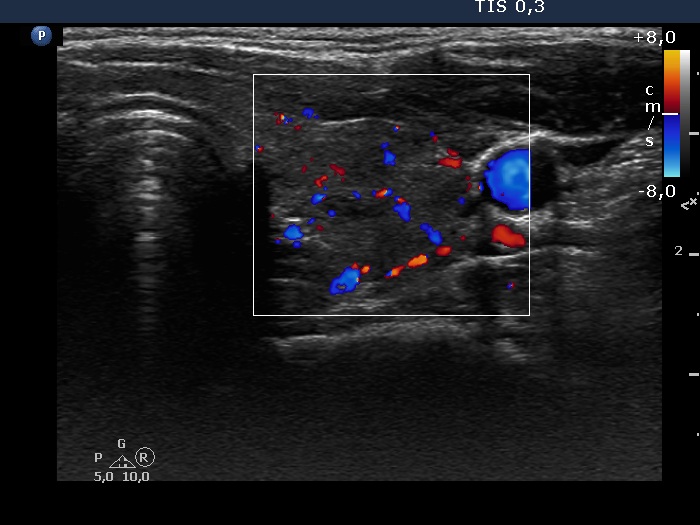

Consecutive patients with the final diagnosis of Hashimoto's thyroiditis - case 56 (1513) (ultrasonographic picture 9)

Left lobe, transverse scan, color Doppler mode. The vascularization is average.